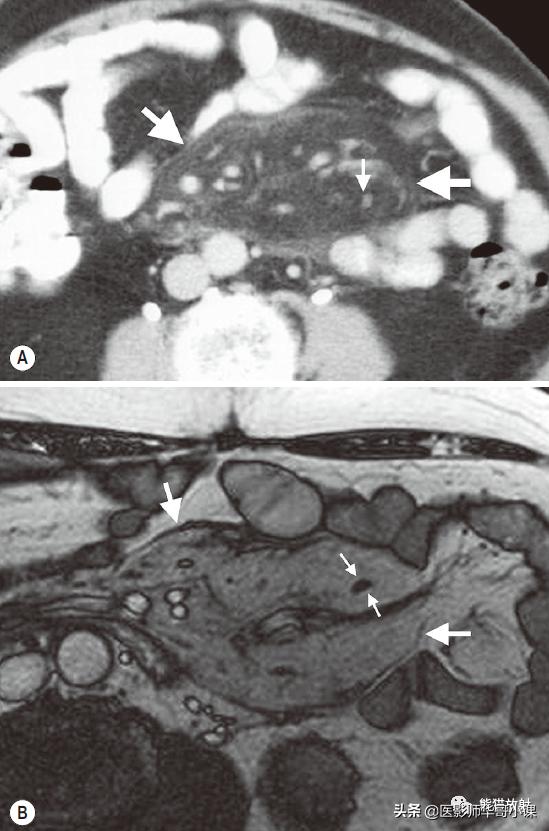

肠系膜脂膜炎的特征性CT表现 为肠系膜根部边界清晰、密度不均的脂肪肿块,包绕肠系膜血管,可推移或不推移邻近肠襻,但不侵犯邻近肠襻,血管周围可见低密度环(图)。T2WI上呈低信号包膜,静脉注射对比剂后可见强化。

回缩性肠系膜炎CT表现 为浸润性软组织密度肿块,周围可见放射状条索影(图),这些特点可能与纤维瘤病或类癌相似。 硬化性肠系膜炎 在T1WI和T2WI图像上均呈低信号,有助于疾病的鉴别。肿块中央坏死区可见钙化(图)。该病有一定的自限性,通常预后较好。

肠系膜脂膜炎。患者腹痛,增强CT(A)和真实稳态进动快速成像(true-FISP) MRI(B) 显示一个边界清晰的脂质肿块(大箭),从小肠系膜根部向左侧腹部延伸,包绕肠系膜血管,无扭转。注意血管周围的晕环(小箭)